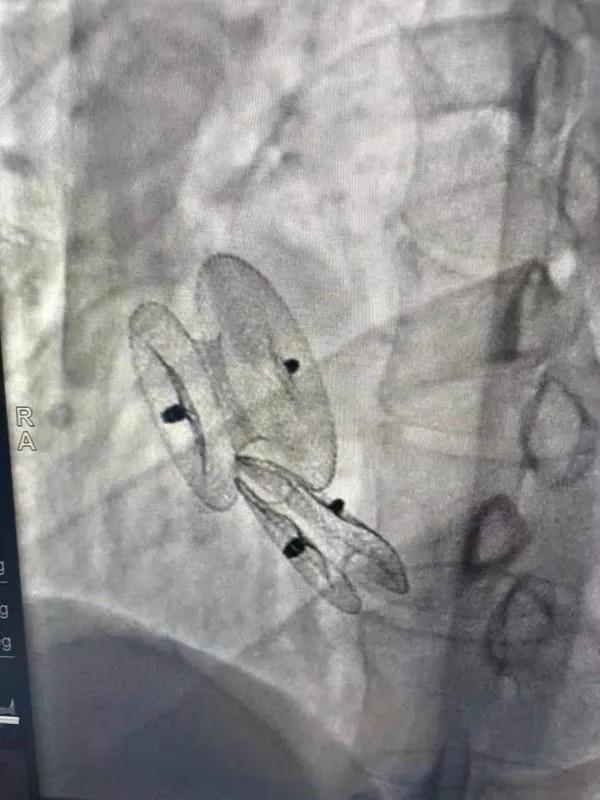

先天性心臟病房間隔缺損呈多孔型怎么辦?患者并非只能選擇開胸手術(shù)。近日,西安國際醫(yī)學(xué)中心醫(yī)院心臟病醫(yī)院成功開展一例雙孔房間隔缺損雙傘介入封堵術(shù)。

房間隔缺損是先天性心臟病的一種,介入手術(shù)相較于傳統(tǒng)的外科手術(shù)損傷小,風(fēng)險相對較低,術(shù)后恢復(fù)快。一般的房間隔缺損多呈單孔,封堵難度較小,而雙孔房間隔的封堵難度大大增加,至今僅有國內(nèi)頂尖的封堵專家成功完成了數(shù)例而已。

患者是位27歲的年輕女性,經(jīng)常感到心慌,心臟超聲發(fā)現(xiàn)房間隔缺損,并且房間隔缺損呈雙孔型,大的約14mm,小的約9mm,兩個缺損間相隔較遠(yuǎn),介入封堵難度非常大。

在詳細(xì)了解患者病情,仔細(xì)閱讀患者影像資料后,曾廣偉主任已經(jīng)有了清晰的手術(shù)策略。在精心的準(zhǔn)備和團隊的配合下,曾主任順利的利用兩個封堵器對房缺進(jìn)行了封堵。